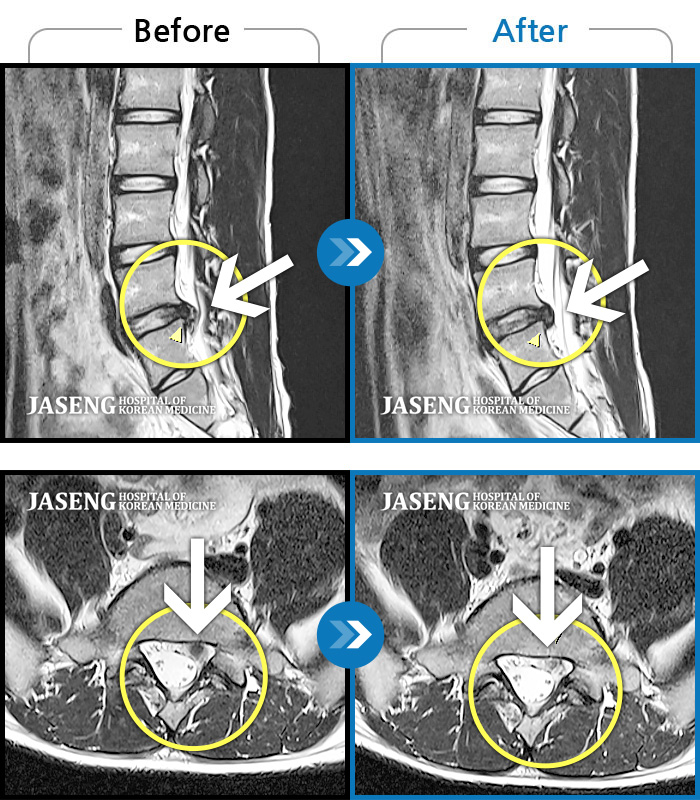

Before

After

환자에게 사전 동의를 받아 동일 조건에서 촬영되었습니다.

개인에 따라 치료 후 부작용이 발생할 수 있으니 의료진과 상담 후 치료를 진행하시기 바랍니다.

오른쪽 정강이 감각이 무디고, 발바닥 통증

요추 5번과 천추 1번 사이에서 탈출된 디스크가 신경막을 압박